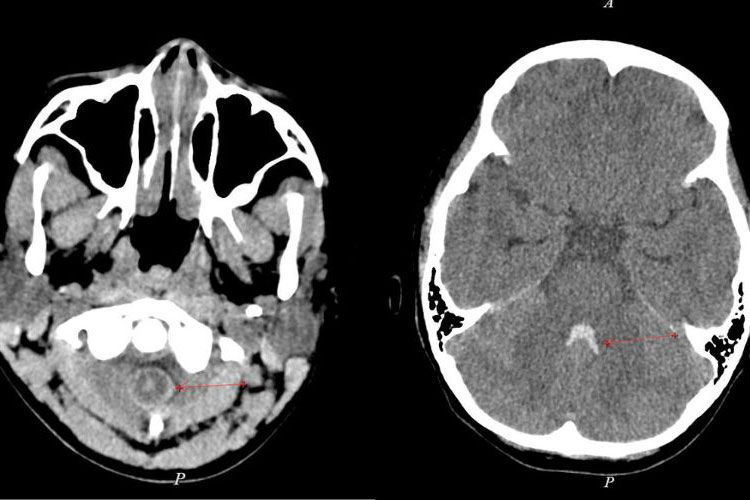

The patient was ordered a brain computed tomography (MSCT), the results showed a large brain hemorrhage in the nucleus pulposus, right temporal, surrounding cerebral edema, and displacement of the brain structure to the left. The patient needed emergency craniotomy to relieve brain compression, remove the hematoma, and stop the bleeding.